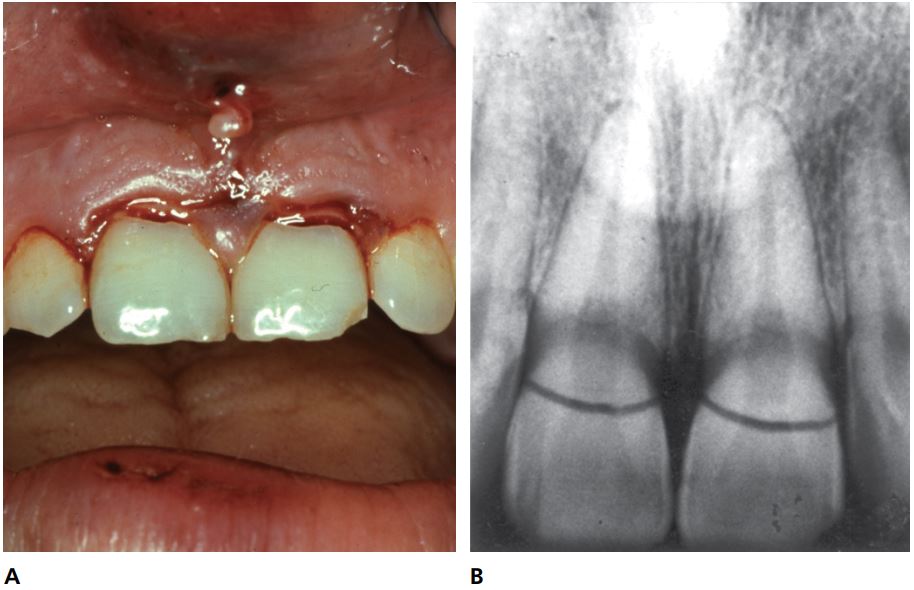

Kiểm tra chụp X quang gãy thân-chân răng thường quy hiếm khi góp phần vào chẩn đoán lâm sàng, vì đường gãy xiên gần như vuông góc với tia (Hình 14.5).

Việc xác định giới hạn đường gãy trong miệng bằng chụp X quang thường khó do các mảnh gãy ở vị trí gần nhau. Mặt khác, giới hạn phía mặt ngoài thì luôn hiện rõ (Hình 14.6).